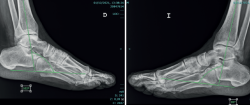

Al año de la rotura del TA, se analizaron las variables demográficas, la escala Achilles Tendon Total Rupture Score (ATRS)(14), la de la American Orthopaedic Foot and Ankle Society (AOFAS)(15), la capacidad de realizar puntillas bi- y monopodales y permanecer en dicha posición durante 3 segundos (Figura 1). Asimismo, se analizó la pérdida del equino fisiológico mediante evaluación clínica con un goniómetro (grados del equino con el paciente en decúbito prono) y se comparó con la extremidad sana (Figura 2). Para evitar sesgos del investigador, se correlacionó esta medida clínica con goniómetro con un estudio radiológico: se realizaron radiografías de ambos tobillos comparativas en posición de decúbito prono con la extremidad en descarga y la rodilla extendida, y se midieron los grados digitalmente con el sistema informático.

Figura 3. Medición del equino residual radiográfico paralela al eje de la tibia y medición del ángulo con respecto a los dos puntos más distales de calcáneo y la cabeza del primer metatarsiano.